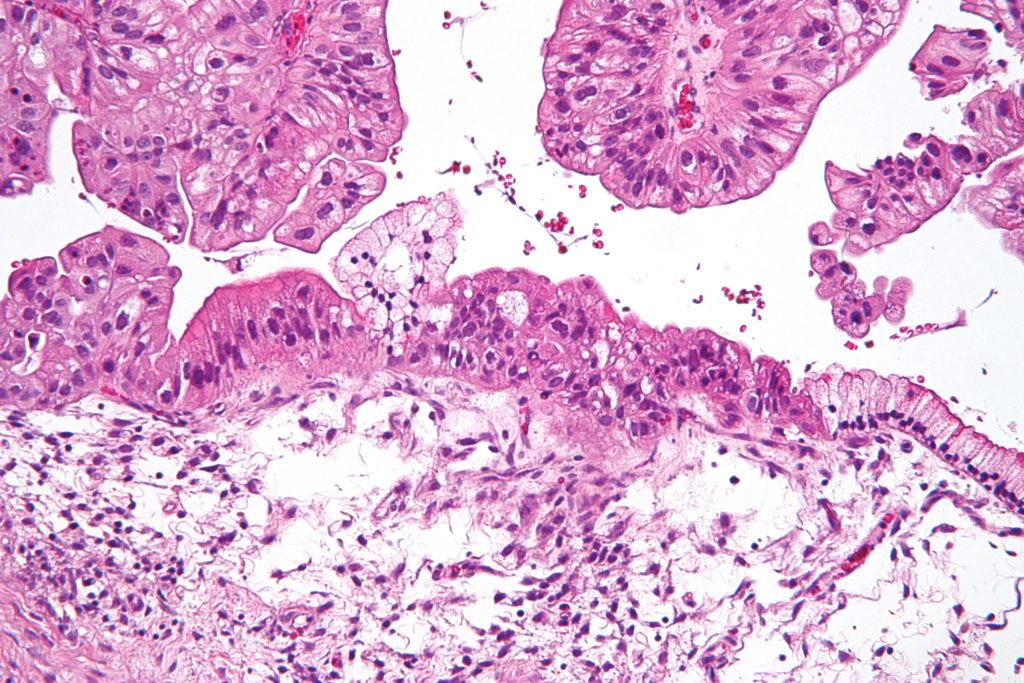

Βλεννώδες κυσταδενοκαρκίνωμα των ωοθηκών

Το βλεννώδες κυσταδενοκαρκίνωμα της ωοθήκης είναι μια σπάνια κακοήθης μορφή των βλεννωδών όγκων των ωοθηκών. Αυτός αντιπροσωπεύει το 5-10% όλων των ωοθηκικών βλεννωδών όγκων. Είναι ένας τύπος ωοθηκικών επιθηλιακών όγκων.

Πολυκυστικός όγκος που δημιουργείται από επιθηλιακά κύτταρα της ωοθήκης και εμφανίζει κοιλότητες που είναι γεμάτος με βλέννη.